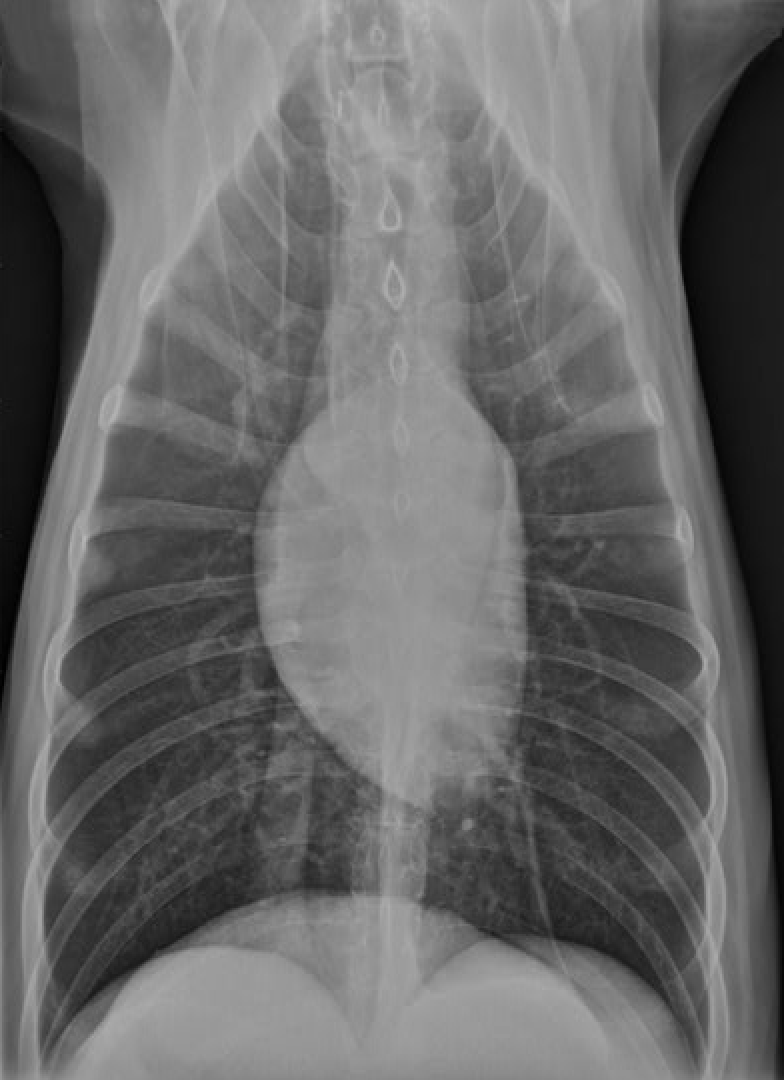

why does the heart appear to sit to the left of the midline in this dorsal ventral radiograph

Because of the size of the right lung

Which chamber of the heart gives rise to the ‘apex’ of the heart?

left ventricle

Where is the apex of the heart?

towards the left of the midline